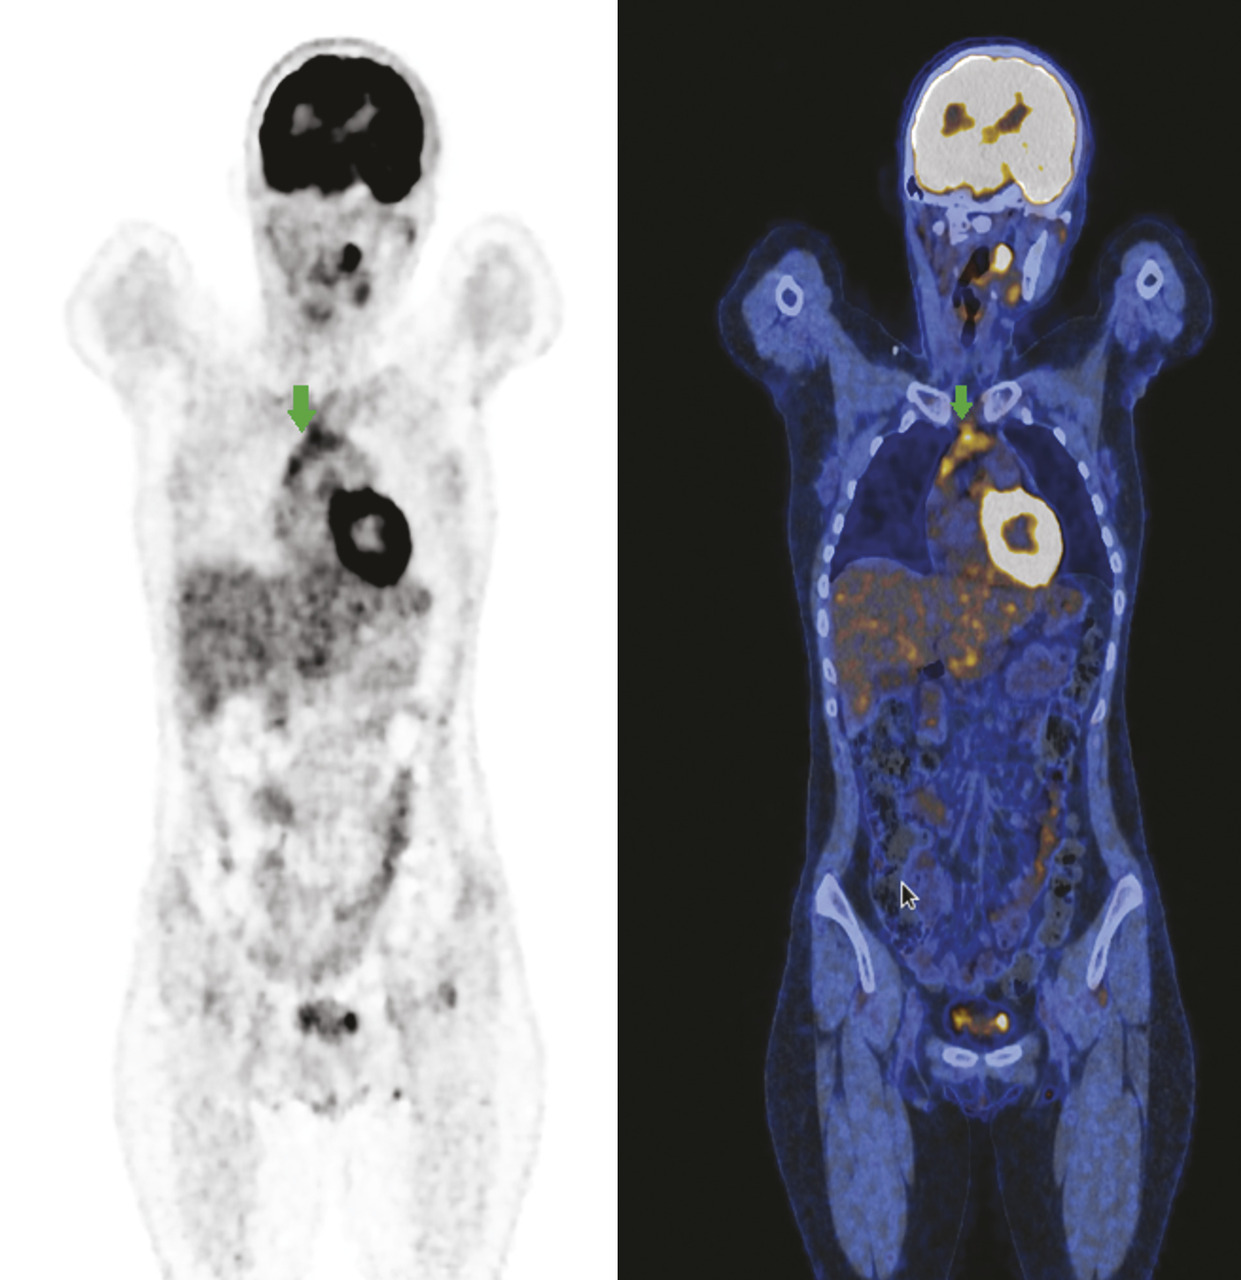

Il faut garder à l’esprit que la fixation à la TEP au 18-FDG est non spécifique du processus tumoral, tout mécanisme inflammatoire étant susceptible de provoquer une hyperfixation à l’imagerie. Il existe de nombreuses situations de faux positifs lors de l’évaluation thérapeutique des lymphomes (rebond thymique, infection concomitante, panniculite mésentérique, maladie inflammatoire telle qu’une sarcoïdose…) [fig. 2 ].

La possibilité d’un faux positif doit être envisagée et évaluée par le médecin nucléaire, notamment du fait de l’impact thérapeutique majeur de ces évaluations (indication d’autogreffe…). En cas de doute, une nouvelle documentation histologique ou une nouvelle TEP de surveillance à distance, à la recherche d’une évolutivité, peuvent être proposées (intérêt de la discussion de ces dossiers en réunion de concertation pluridisciplinaire [RCP] incluant imageurs et cliniciens).

Il faut garder à l’esprit que la fixation à la TEP au 18-FDG est non spécifique du processus tumoral, tout mécanisme inflammatoire étant susceptible de provoquer une hyperfixation à l’imagerie. Il existe de nombreuses situations de faux positifs lors de l’évaluation thérapeutique des lymphomes (rebond thymique, infection concomitante, panniculite mésentérique, maladie inflammatoire telle qu’une sarcoïdose…) [